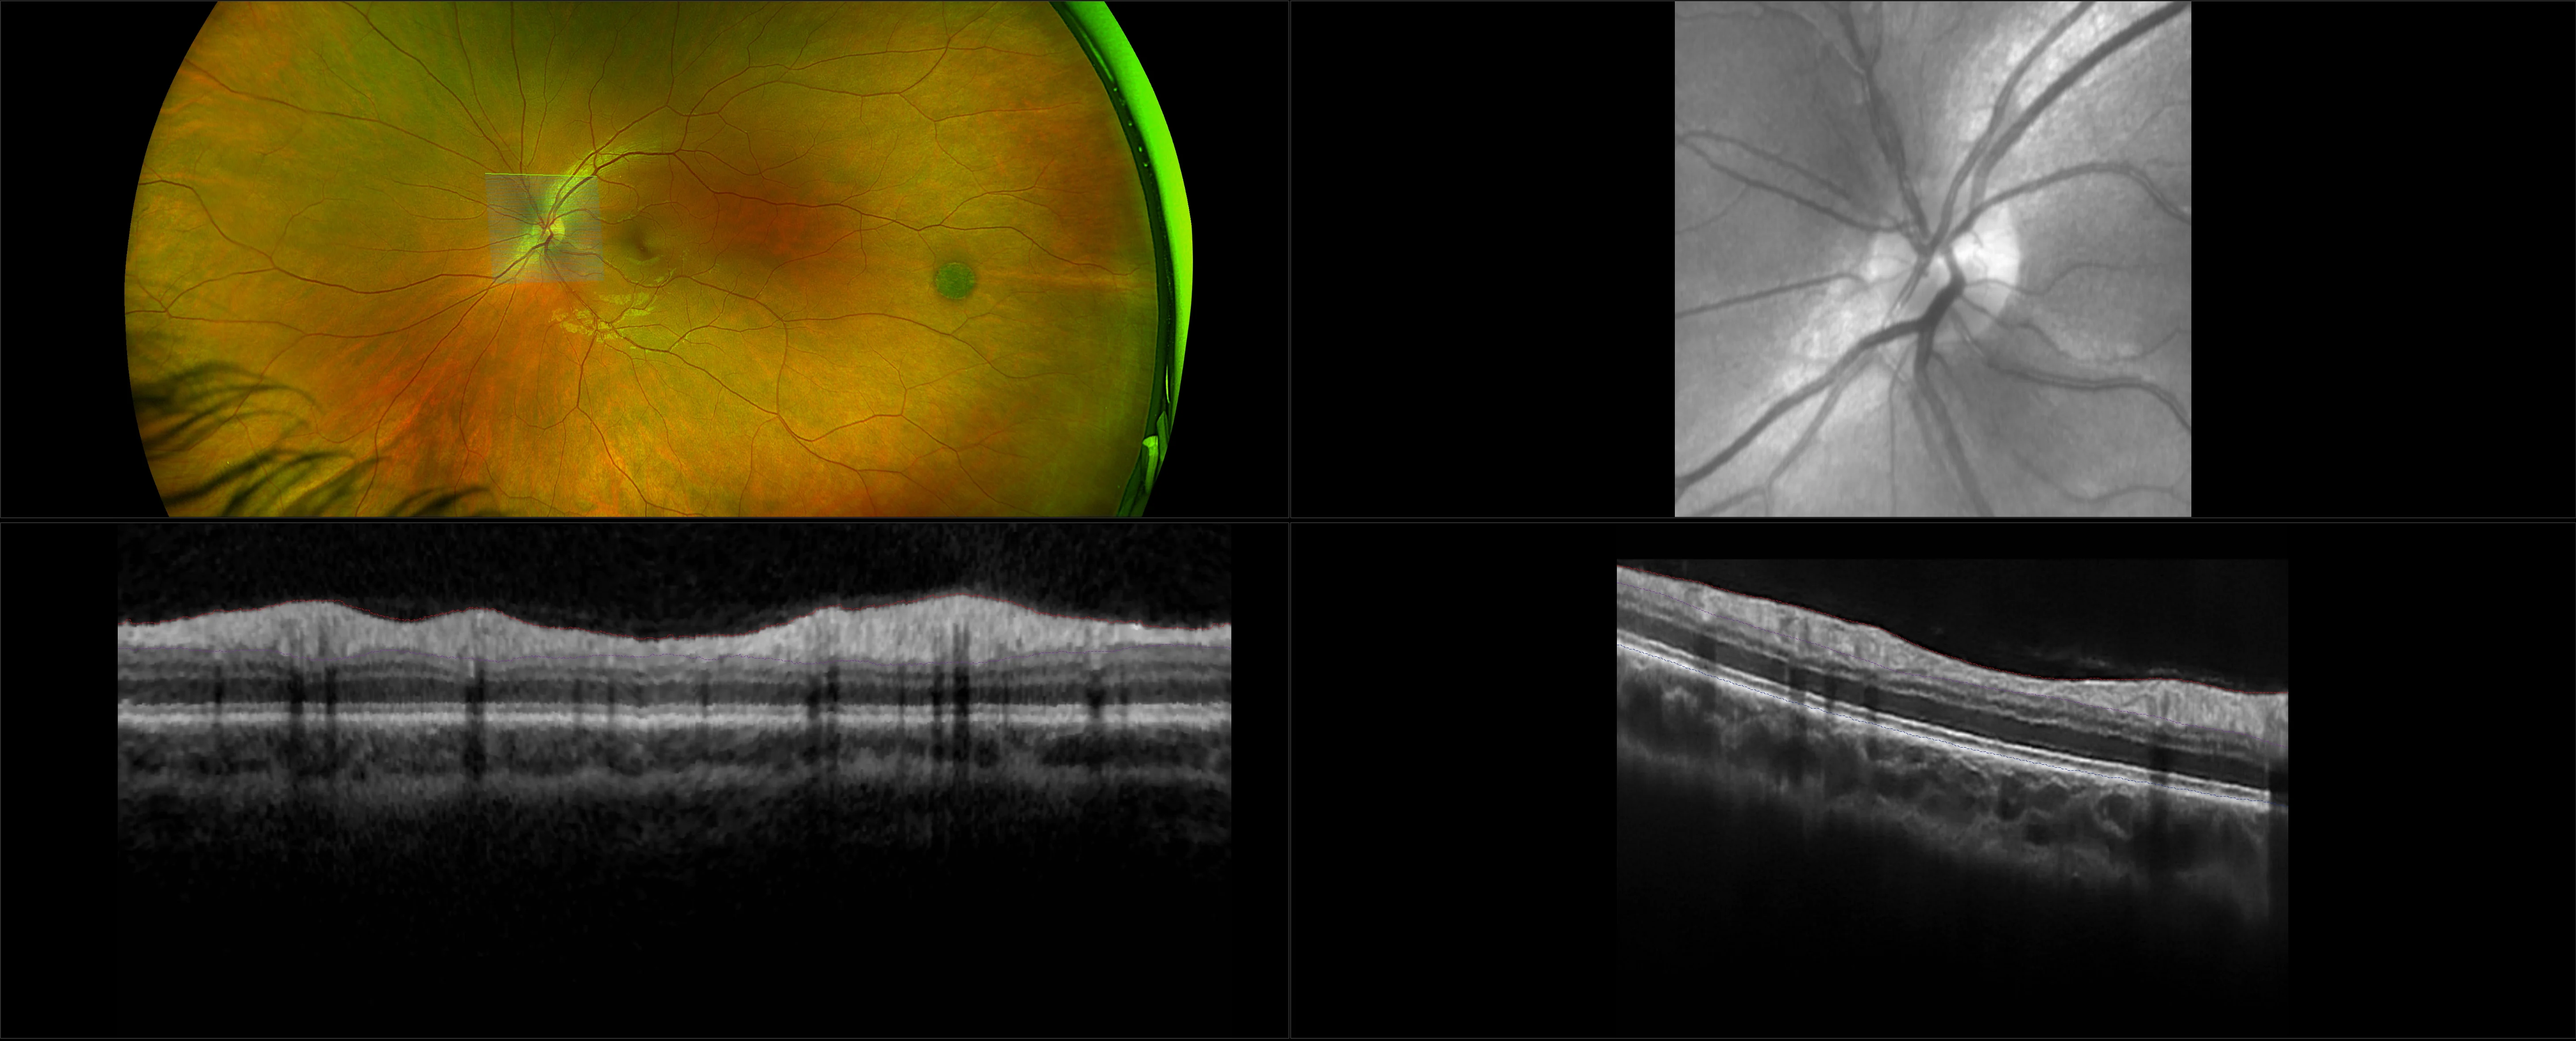

optomap images representing other retinal disease not found in common categories of pathology.